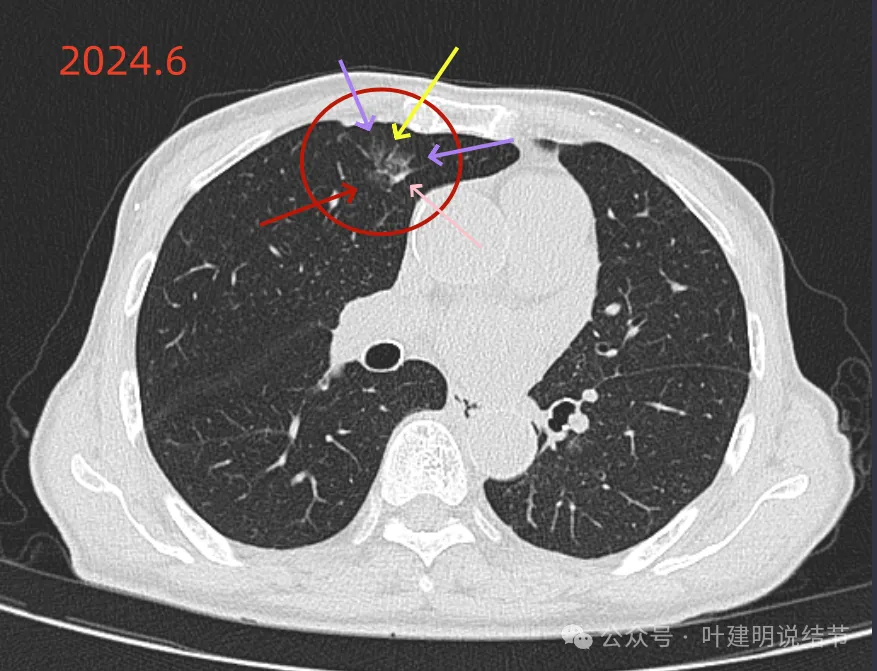

先来看2024年6月某省级医院的影像:‘

这个病灶是混合密度,边缘毛糙有细毛刺,毛刺较锐利,灶内有细支气管通气征,整体轮廓较清。如果之前也有在的,则基本上肯定是肺癌,而且至少是微浸润性腺癌。